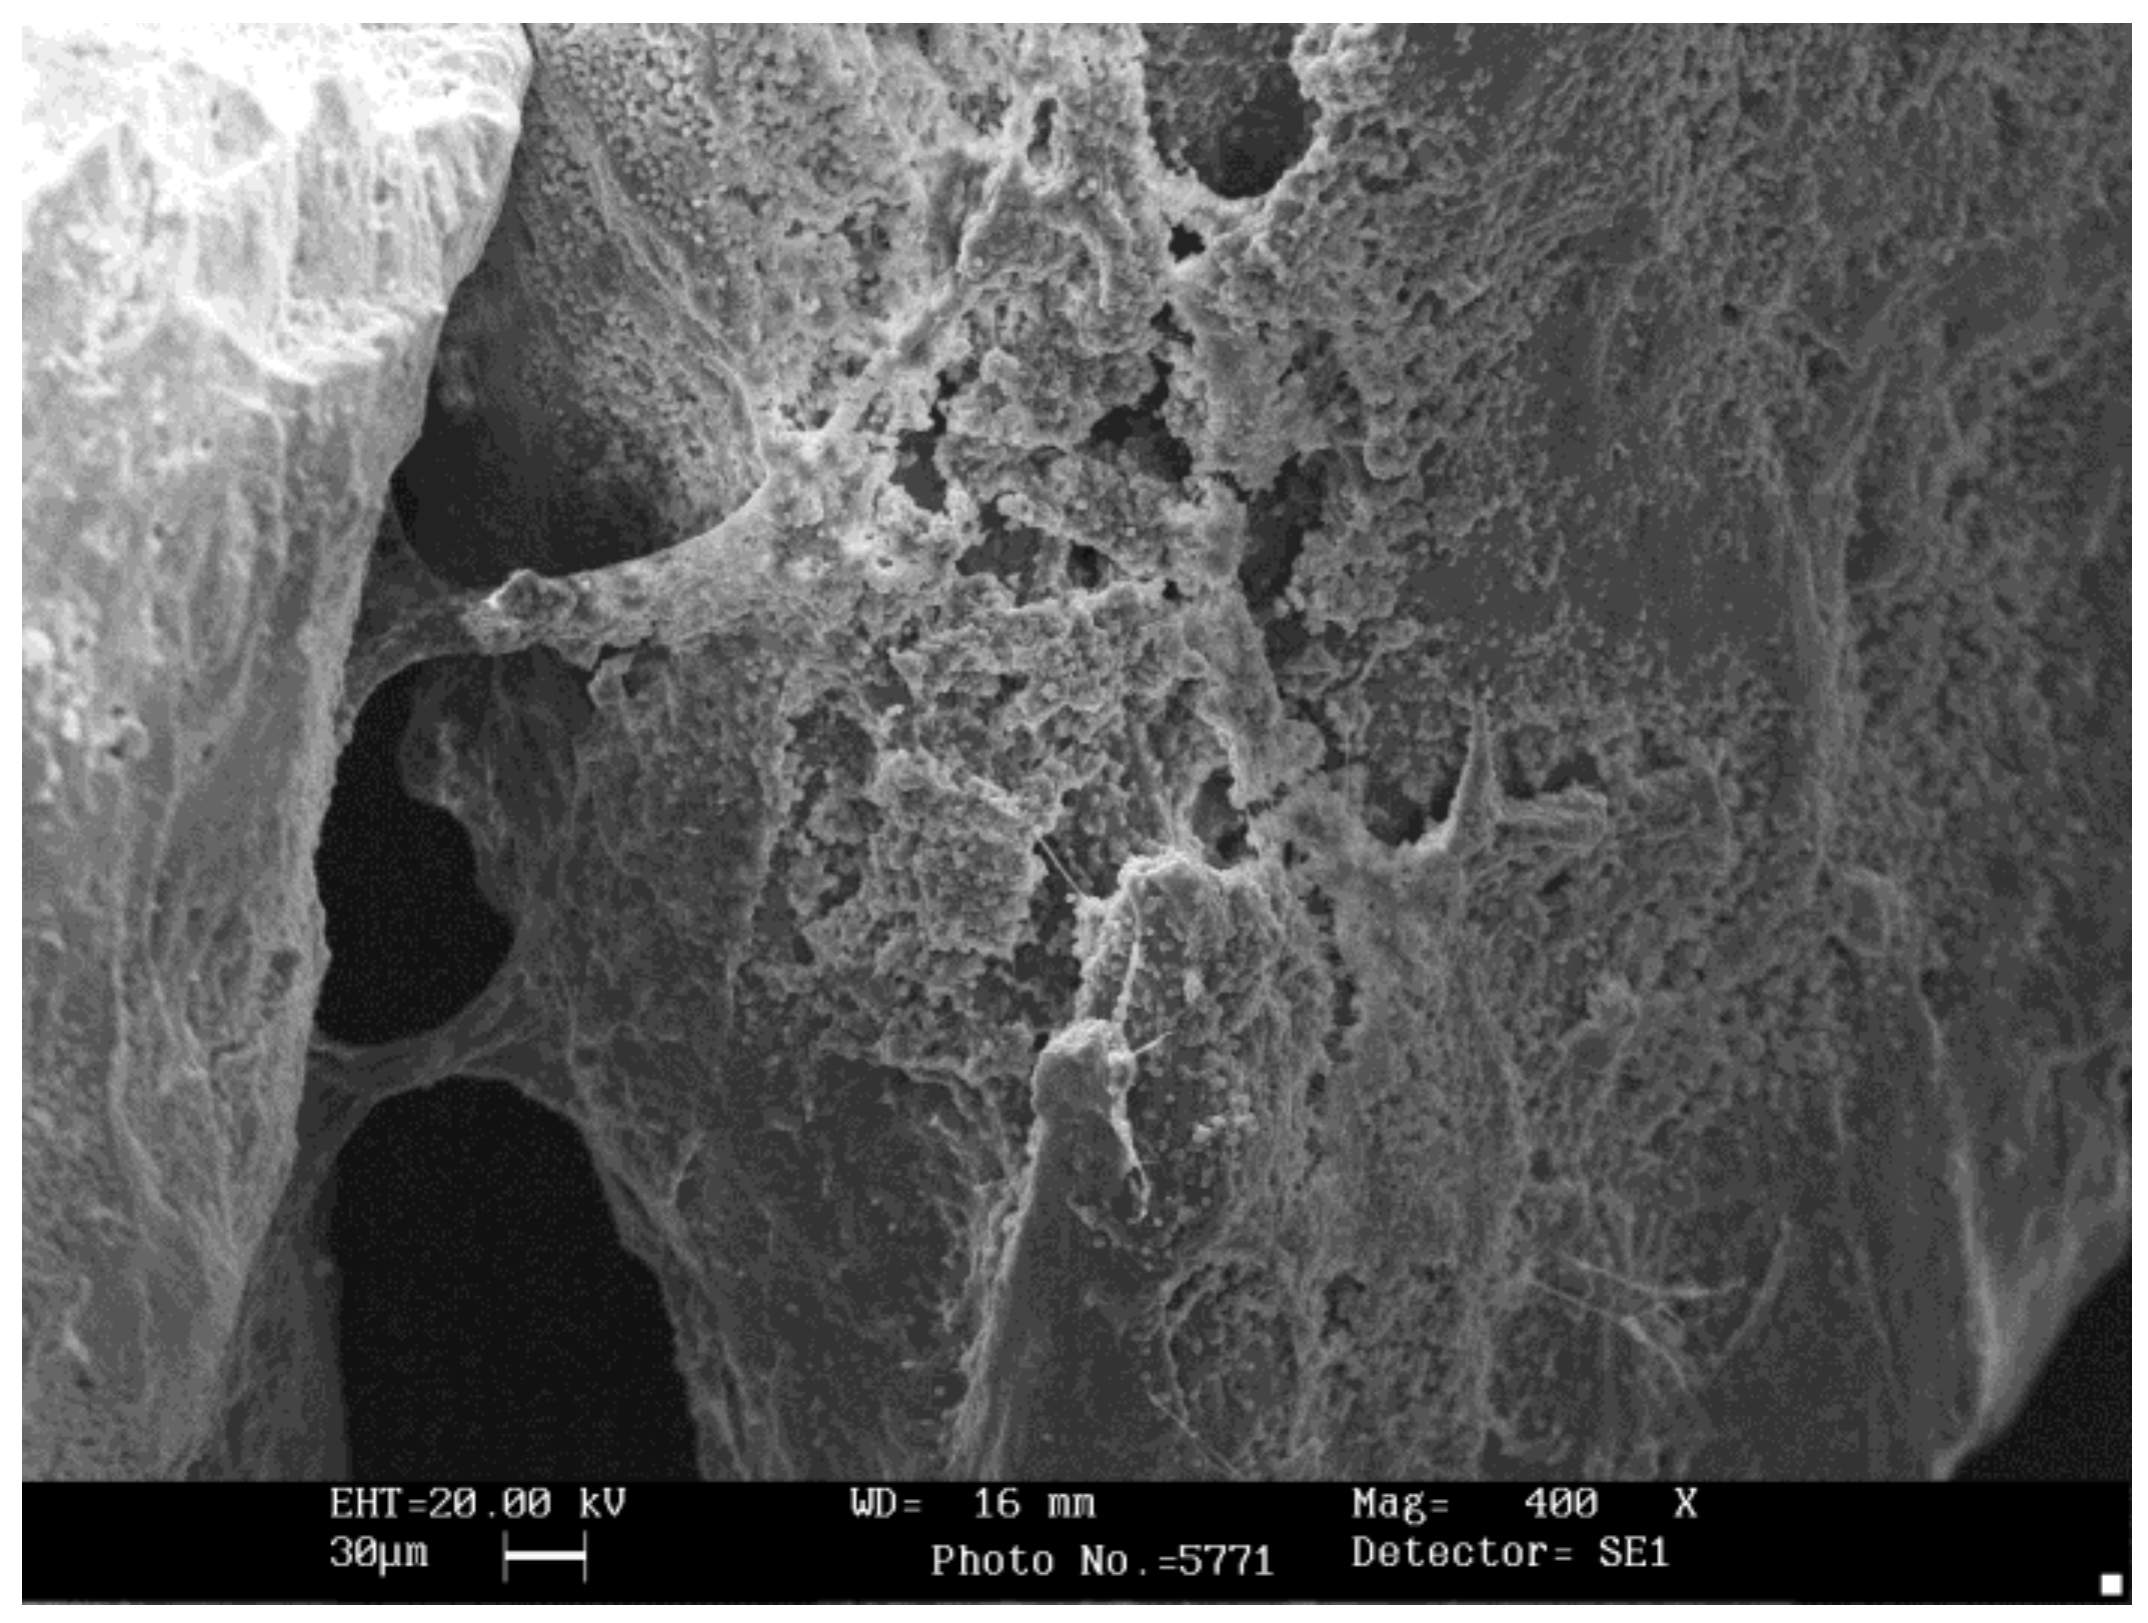

2.2. Scanning Electron Microscopy